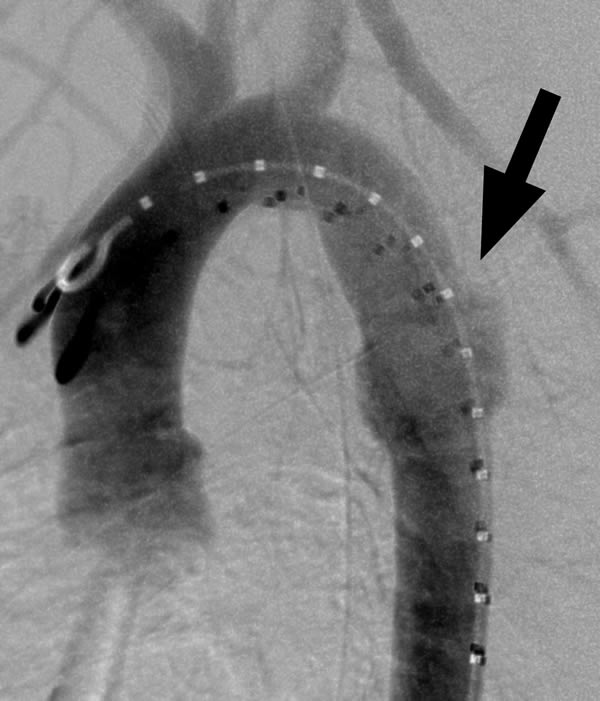

The modified original delivery sheath is then inserted snuggly into the hub of the long 16- or 18-French sheath over the guidewire. The endograft is transferred into the new sheath by advancing the delivery catheter while ensuring that the end of the original sheath is tightly nested in the receiving sheath. The original delivery system is then removed over the guidewire. The blunt back end of the dilator from the new sheath is inserted over the guidewire and used to push the endograft to the end of the long delivery sheath. The 5-French pigtail catheter is re-advanced into the distal aortic arch and control angiograms are obtained through the 5-French pigtail catheter prior to deployment of the endograft (Figure 3A). The endograft is deployed by withdrawing the sheath while maintaining the endograft in a fixed position with the pusher catheter. Angiograms are obtained through the 5 French pigtail catheter before and after gentle inflation of appropriate sized angioplasty balloons within the endografts (Figure 3B).

Figure 3a: Pre- and post-deployment digital subtraction angiograms (DSA) of transected aorta. Pre-deployment DSA with a 22-mm diameter stentgraft advanced to the end of the 18-French sheath (black arrow) using the back end of the sheath dilator as a pusher (white arrow). The endograft was repositioned prior to deployment.